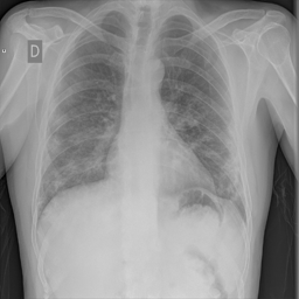

Research is based on the second update of the "COVID-19 Radiography Database" Chowdhury et al. (2020); Rahman et al. (2021); Cov (2022) developed by a team of researchers from Qatar University, Doha, Qatar, and the University of Dhaka, Bangladesh along with their collaborators from Pakistan and Malaysia in collaboration with medical doctors. The database incorporates posterior-to-anterior (AP)/anterior-to-posterior (PA) chest X-ray images from multiple public sources Vayá et al. (2020); Winther et al. (2020); SIR (2020); Cohen et al. (2020a, b); Haghanifar et al. (2022); RSN (2018); Kermany et al. (2018) and contains: 3616 images of COVID-19-positive cases, 6012 images of lung opacity (non-COVID lung infection), 1345 images of viral pneumonia, 10192 images of healthy lungs. Images are provided after conversion to common PNG format with 256x256 dimensions. For each image, the dataset authors provided a corresponding lung segmentation mask obtained using a dedicated U-Net model Rahman et al. (2021). Sample images from the database are presented in Fig. 2.

Images in the original dataset are not framed consistently, with body parts visible in the image tending to differ depending on the original source. In order to remove this possible bias all images are cropped to a rectangular region of interest encompassing the corresponding lung mask. After cropping the images are resized to a common size of 128x128 pixels. An example of cropped and rescaled image is presented in Figs. 2f and 2g. Finally, the pixel values are normalised to [0; 1] scale. All images are grayscale with three channels present, such format is retained as an input for the classification networks as this is the format they were trained on originally. For the GAN training, a single-channel grayscale format is used which leads to faster execution.

Many images in the dataset contain annotations or marks made during the image acquisition or afterwards by a radiologist. Examples of such images are presented in Fig. 3. Such symbols in the training dataset are known to generate biases as classifiers tend to target their attention to the presence of the symbols instead of genuine features of the image Rajaraman and Antani (2020); DeGrave et al. (2021). Therefore after the initial preprocessing, consisting of cropping and resizing all images containing such elements were removed.